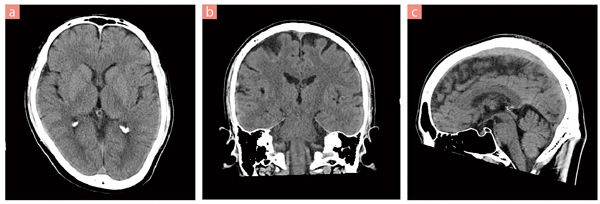

■症例1 頭部スクリーニング

a:axial像,b:coronal像,c:sagittal像 80列,コンベンショナル撮影。

わずか4回転で頭部撮影を終了。